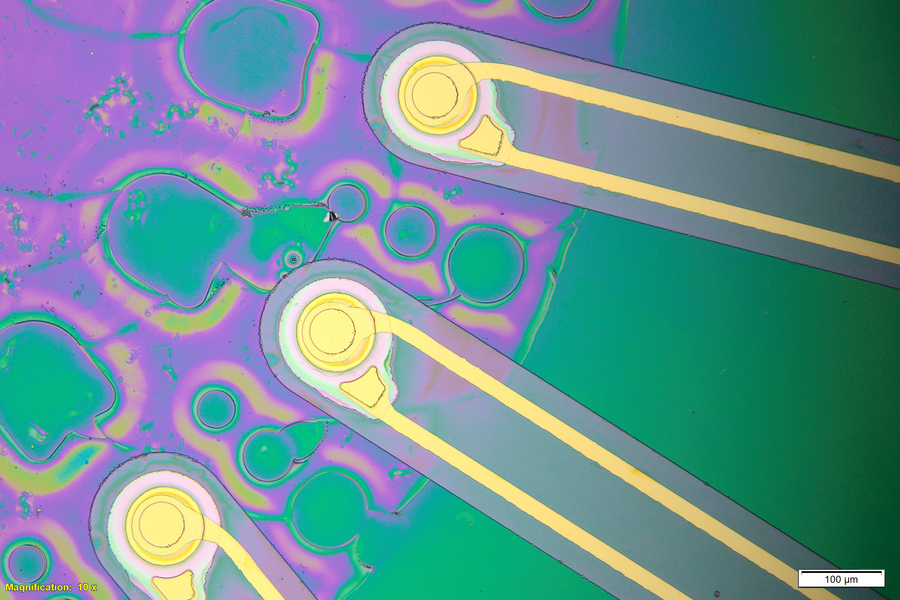

- Ultrasound Waves in Acoustic Microscopy